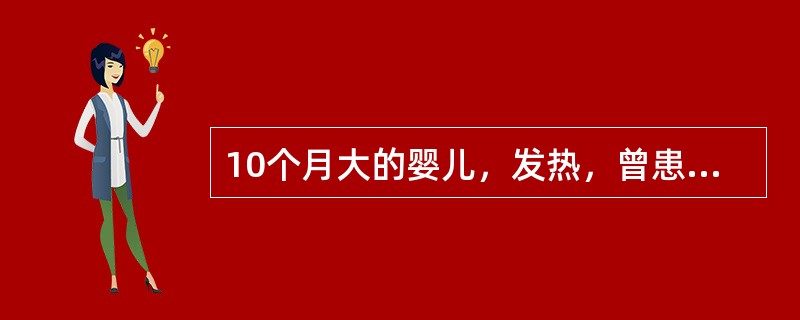

10个月大的婴儿,发热,曾患中耳炎,CT扫描如图所示,正确的描述或诊断是()

A.咽后壁软组织肿胀

B.其内密度不均

C.颈椎骨质未见明显异常

D.咽后壁脓肿

E.咽后壁寒性脓肿

[多选题]10个月大的婴儿,发热,曾患中耳炎,CT扫描如图所示,正确的描述或诊断是()A.咽后壁软组织肿胀B.其内密度不均C.颈椎骨质未见明显异常D.咽后壁脓肿

[多选题] 10个月大的婴儿,发热,曾患中耳炎,CT扫描如图所示,正确的描述或诊断是()A .咽后壁软组织肿胀B .其内密度不均C .颈椎骨质未见明显异常D .咽后壁脓肿E .咽后壁寒性脓肿

[多选题] 10个月大的婴儿,发热,曾患中耳炎,CT扫描如图所示,正确的描述或诊断是()A . 咽后壁软组织肿胀B . 其内密度不均C . 颈椎骨质未见明显异常D . 咽后壁脓肿E . 咽后壁寒性脓肿